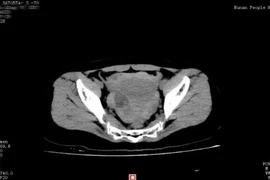

Suýt chết vì vỡ u nang buồng trứng khi 'yêu'

Một phụ nữ Trung Quốc đã mất khoảng 40% lượng máu cơ thể vì vỡ u nang buồng trứng sau khi làm "chuyện ấy".